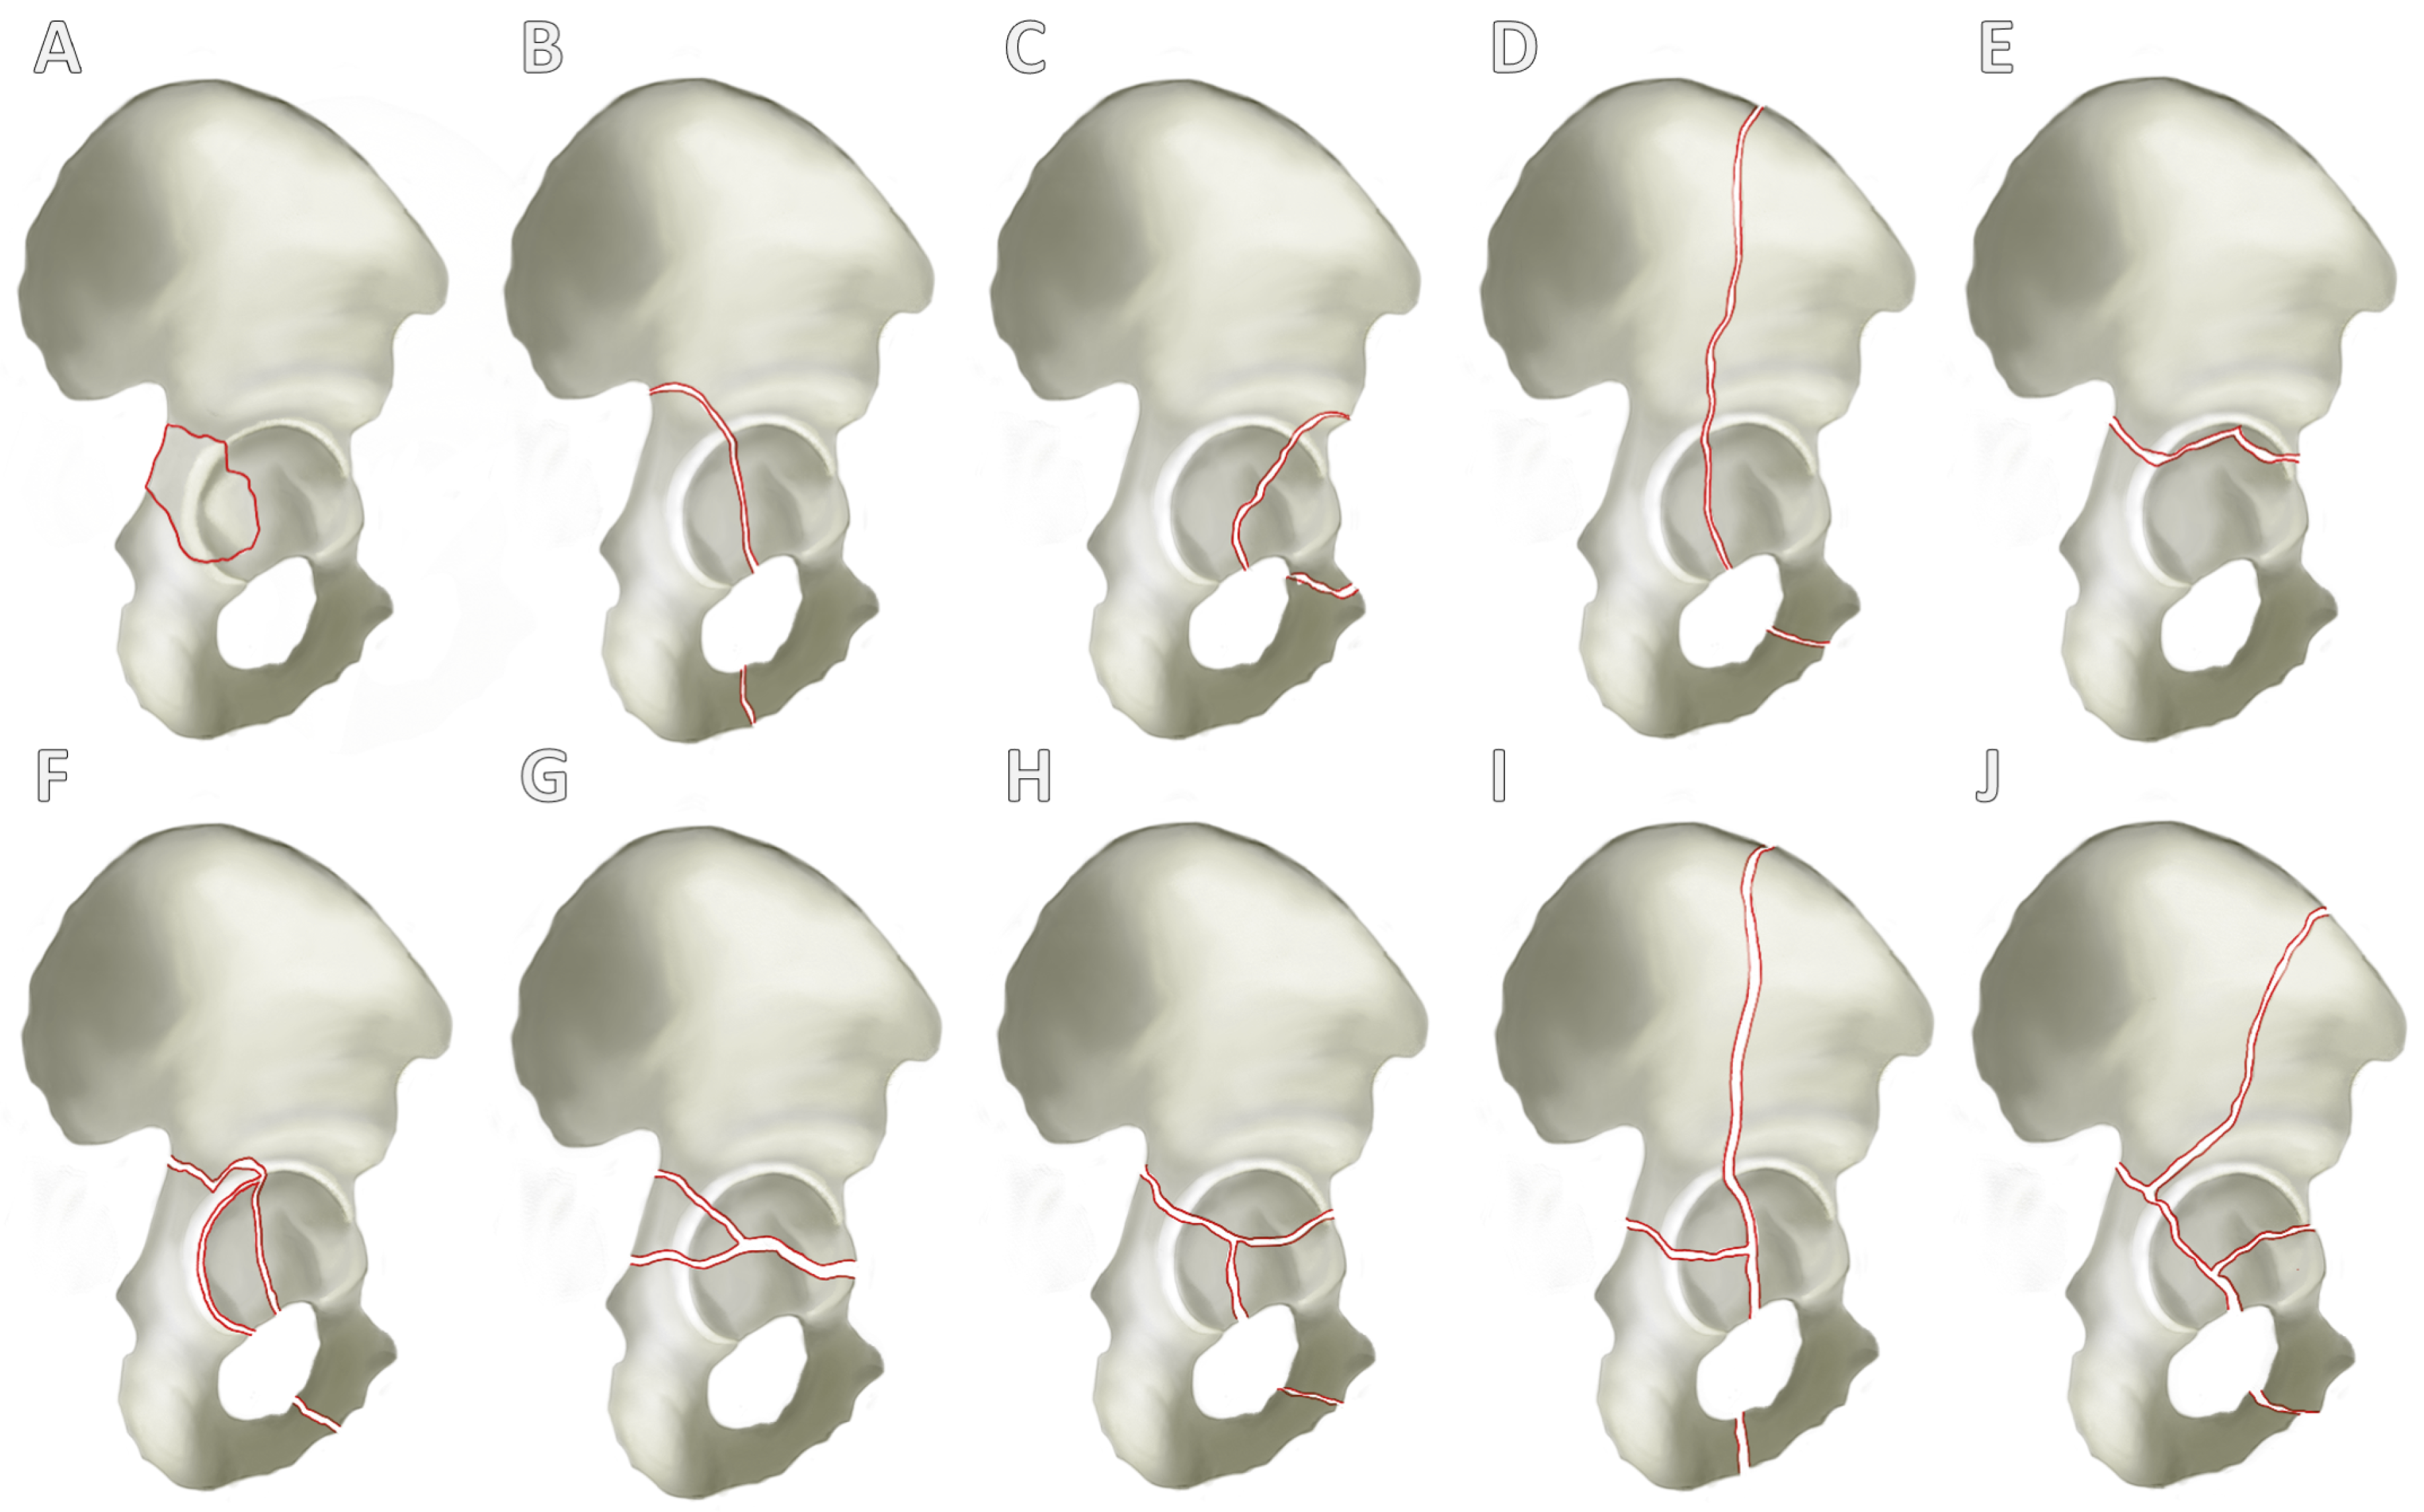

Alongside medical history and physical examination, radiological imaging techniques play a key role in the diagnosis of acetabular fractures. Both X-ray examination in the anterior–posterior, ala, and obturator beam of the pelvis and CT are used as standard procedures and are highly recommended [27] (Figure 3).

If an acetabular fracture cannot be ruled out with certainty in the X-ray examination, a CT scan should be performed. CT is not only used to confirm the diagnosis but also to categorize the fracture as described above (Figure 3B–D). CT can therefore be used to categorize the fracture and plan the surgical treatment. It is important to know the classification, as the approach is determined in the planning phase after the diagnosis and categorization.

Figure 3. X-ray and CT diagnosis of a geriatric acetabular fracture. Initially, the left-sided acetabular fracture can be recognized in the anterior–posterior radiograph of the pelvis (A). A CT scan was added for fracture classification and preoperative planning (BD). It revealed a T-shape fracture (BD).